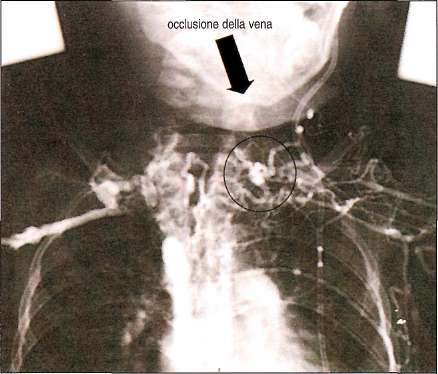

Flebografia